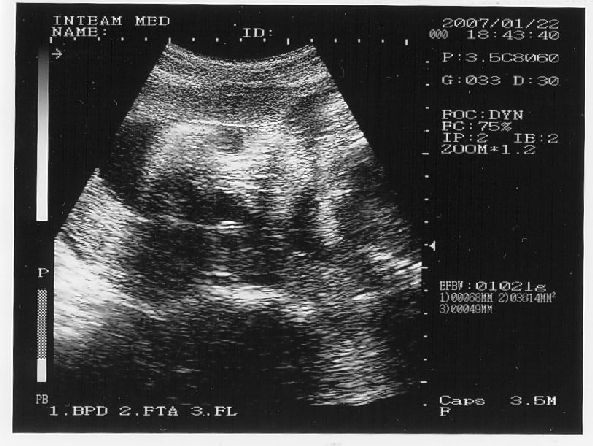

Tényleg tündéri pofija van, nagyon megható lehetett látni. Gondolom sokkal szívhez szólóbb, mint mikor az egész babát látni. Ez már személyesebb lehet.

Gabi baba arcocskája

Gabi baba arcocskája  Gabi baba kukaca

Gabi baba kukaca